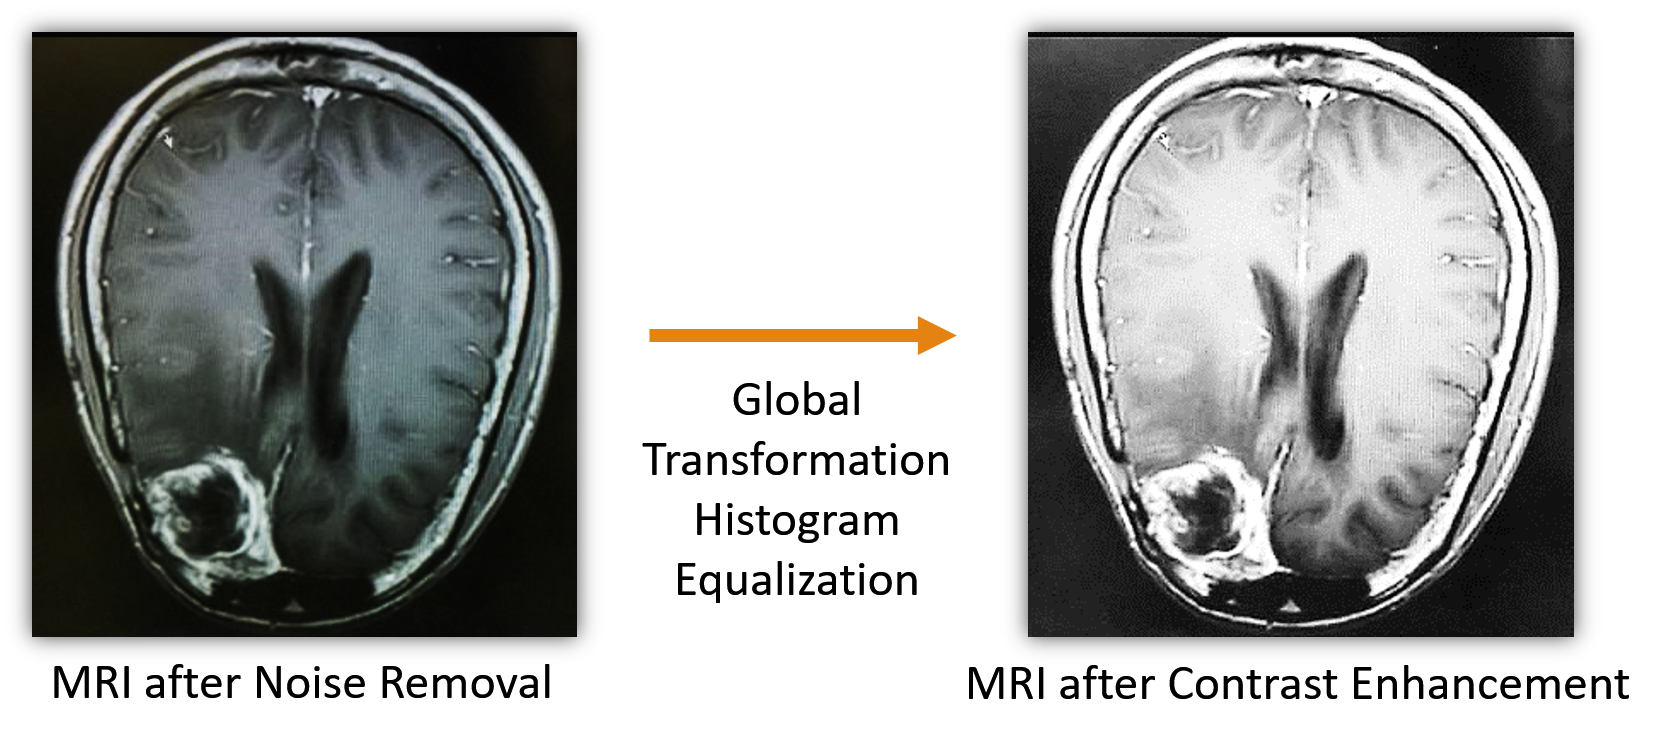

Contrast enhancement: A Gaussian filter might hamper the image brightness and contrast. Hence, a contrast optimization procedure is required. The contrast of an image is the difference in the luminance of various sections in the image. An optimal contrast-enhanced image will be able to show every object present in the image. The need for contrast enhancement technique in medical field images kotkar2013review are of utmost importance. Local and global transformation techniques kabir2010brightness prove to be the best options in this regard as they tend to maintain the mean brightness and does not inject undesirable artifactskotkar2013review . Global Transformation Histogram Equalization is used for contrast enhancement in this work. The global transformation function formulated in Eqn. 3 is used for contrast enhancement. Here, T(g)𝑇𝑔T(g) being the global transformation function, where g denote its intensity, gminsubscript𝑔𝑚𝑖𝑛g_{min} and gmaxsubscript𝑔𝑚𝑎𝑥g_{max} defines the lower and upper bounds of the histogram partitions; here, x as intensity value, h(x) denotes the histogram count.

T(g)=gmin+(gmaxgmin)(x=gmingh(x)x=gmingmaxh(x))𝑇𝑔subscript𝑔𝑚𝑖𝑛subscript𝑔𝑚𝑎𝑥subscript𝑔𝑚𝑖𝑛superscriptsubscript𝑥subscript𝑔𝑚𝑖𝑛𝑔𝑥superscriptsubscript𝑥subscript𝑔𝑚𝑖𝑛subscript𝑔𝑚𝑎𝑥𝑥T\left(g\right)=g_{min}+\left(g_{max}-g_{min}\right)\left(\frac{\sum_{x=g_{min}}^{g}h\left(x\right)}{\sum_{x=g_{min}}^{g_{max}}h\left(x\right)}\right) (3)

An example showing the contrast enhancement using Global Transformation Histogram Equalization is shown in Fig. 4.

Refer to caption

Figure 4: Example of contrast enhancement in MRI image